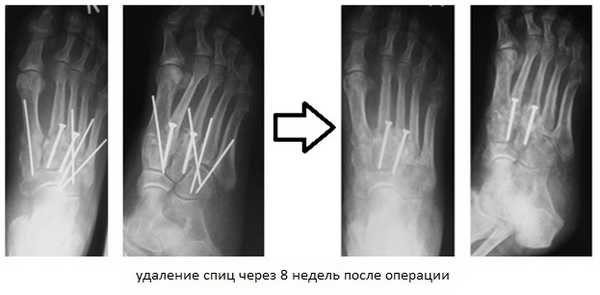

При смещении более 2 мм, нестабильности при функциональных тестах – рекомендовано открытое устранение вывиха с жёсткой фиксацией винтами или пластинами. Используются один или два продольных доступа в 1 и 2 межплюсневых промежутках. После обнажения первого предплюсне-плюсневого сустава первым этапом устраняется межклиновидная нестабильность, вторым этапом устраняется предплюсне-плюсневая нестабильность. В послеоперационном периоде сразу начинается разработка активного объёма движений. Нагрузку на стопу начинают постепенно, с тем чтобы полностью её восстановить к 6-8 неделе. Удаление спиц Киршнера производится через 6-8 недель, компрессирующих винтов через 3-6 месяцев. Возвращение к полной физической активности не ранее 9-12 месяцев после операции.

После операции следует 6-12 недельный период иммобилизации в жёстком ортезе без осевой нагрузки на ногу. Затем нагрузка постепенно увеличивается до полной в течение 4-6 недель.